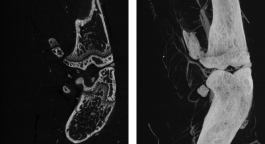

Slice view (on left) and MIP (on right)

Volumetric image dataset can shown as single slices or as a slab in which the maximum, minimum, or average values within a slab thickness are displayed. These types of images can improve interpretation accuracy and decrease review time.